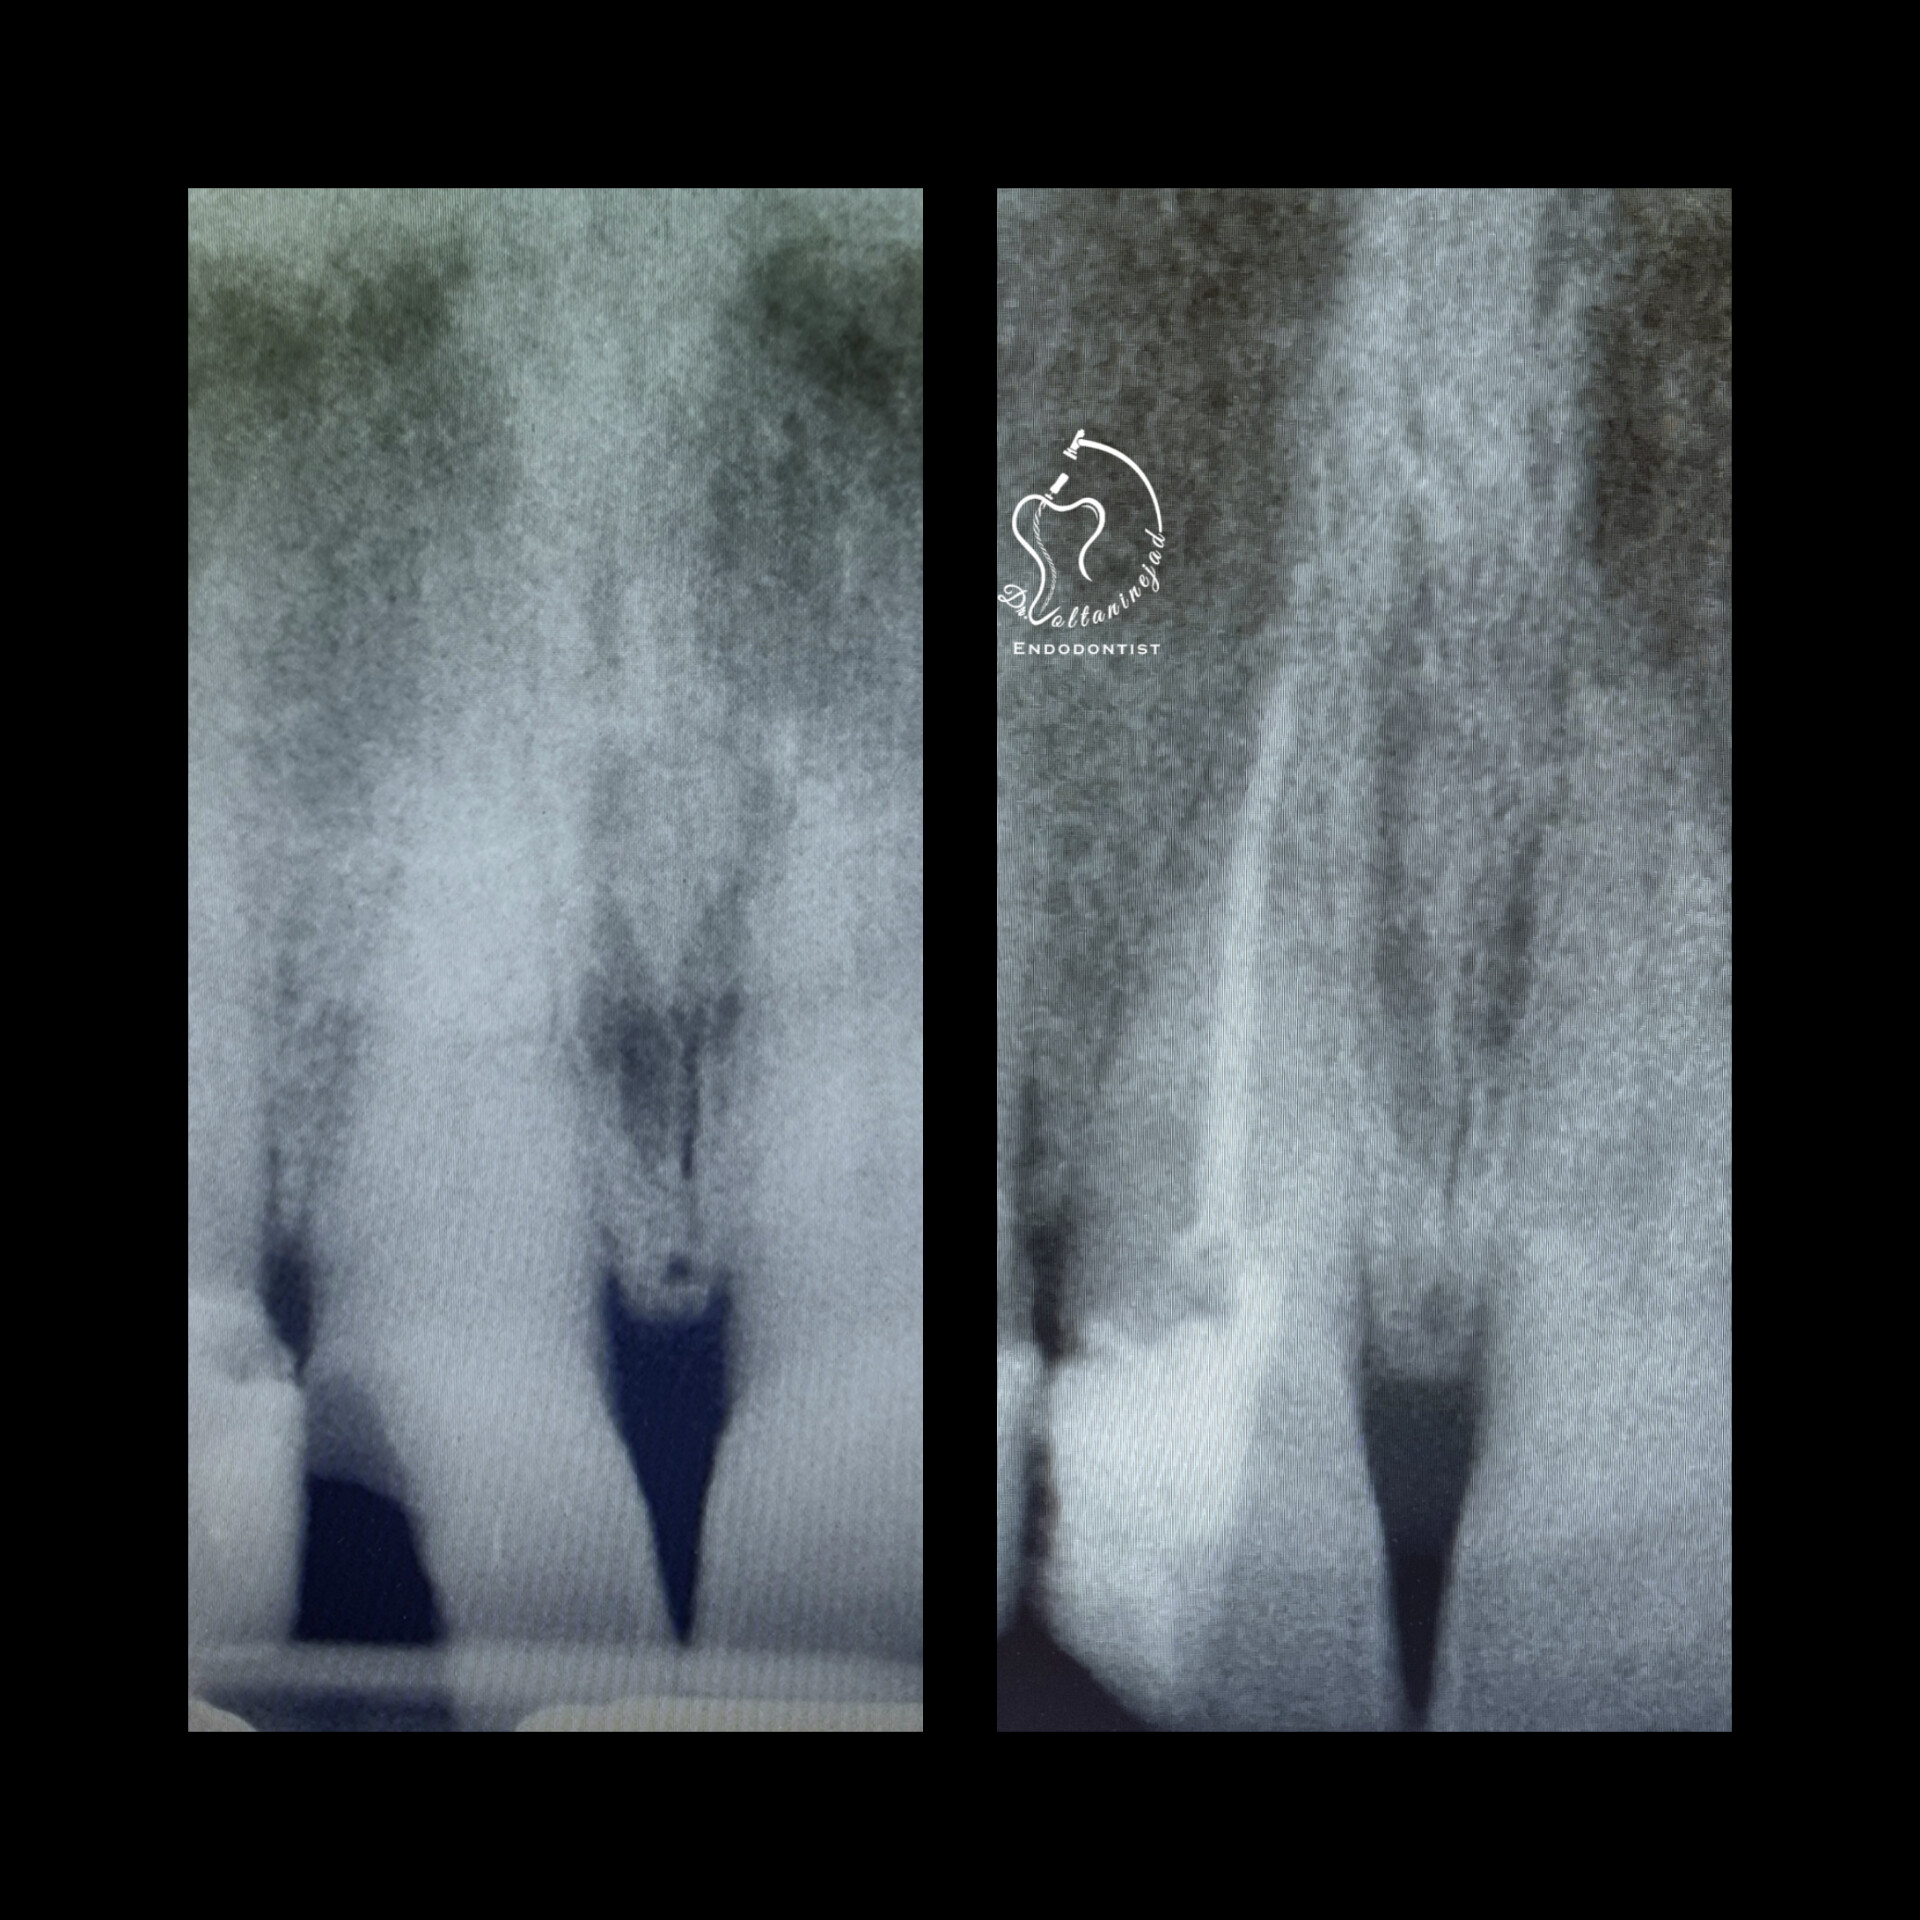

🔹 درمان ریشه دندان دائمی نابالغ با انتهای ریشه باز و آبسه مزمن در کودک ۸ ساله

• شرح کوتاه: کودک ۸ ساله با دندان دائمی نابالغ عفونی و آبسه مزمن مراجعه کرد که درمان ریشه تخصصی میکروسکوپی با موفقیت انجام شد.

• نتیجه: حذف ضایعه مقاوم و حفظ دندان به مدت طولانی.